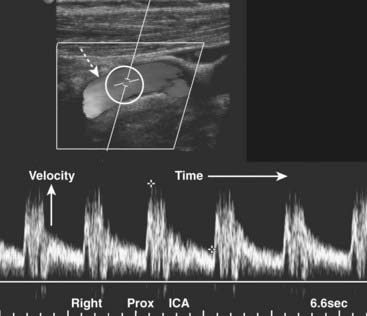

image Vascular ultrasound studies combine morphologic images of the vessels with the simultaneous recording of the velocity of flow displayed by the Doppler spectral waveform.

The combination of the two is called Duplex sonography, and its use helps assure that the sample being measured accurately represents the area of interest.

imageThe Doppler spectral waveform is a graphic representation of the velocity of flow over time within a focused area. It is depicted along an x (time) and y (velocity) axis. Flow toward the transducer is displayed above the baseline; flow away below the baseline. Different arteries have distinctive spectral waveforms depending, in part, on whether there is normally a high or low resistance to flow within them.

image Color flow Doppler imaging adds the dimension of superimposing moving blood (shown in color) over a gray-scale image of the anatomic structure enabling a more rapid identification of potential abnormalities. The Doppler spectral waveform quantitates the flow.

image Carotid ultrasonography has become the study of choice for the noninvasive assessment of extracranial atherosclerotic disease. Extracranial carotid occlusive disease accounts for more than one half of strokes. Carotid ultrasound is also used to evaluate bruits, as preoperative screening prior to other major vascular surgery and to assess the patency of the vessel after endarterectomy (Fig. 19-30).

image

Figure 19-30 Normal proximal right internal carotid artery, duplex sonogram.

The upper display (dotted white arrow) depicts flow in the artery (the original displayed the flow in color). Within the white circle is the Doppler sampler volume, the measurements for which are shown on the lower graphical display, called the Doppler spectral waveform. The x axis represents time; the height of the waveforms represents the velocity of blood flow within the Doppler sampler volume. The velocity normally increases with each systole and decreases with each diastole.

imageCarotid stenosis begins to cause elevations in the velocity of flow when there is greater than 50% narrowing of the lumen. Significant stenosis alters the Doppler waveform proximal, at, and distal to the point of stenosis.

image Ultrasound is used to assess the thickness of the vessel wall (it gets thicker with atherosclerosis), the presence and nature of plaque, and analysis of the Doppler spectral waveform.